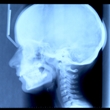

Muenke syndrome is a rare genetic disorder characterized by craniosynostosis, or premature closure of certain bones in the skull. This affects the shape of the face and head. Muenke syndrome is typically detected during infancy.